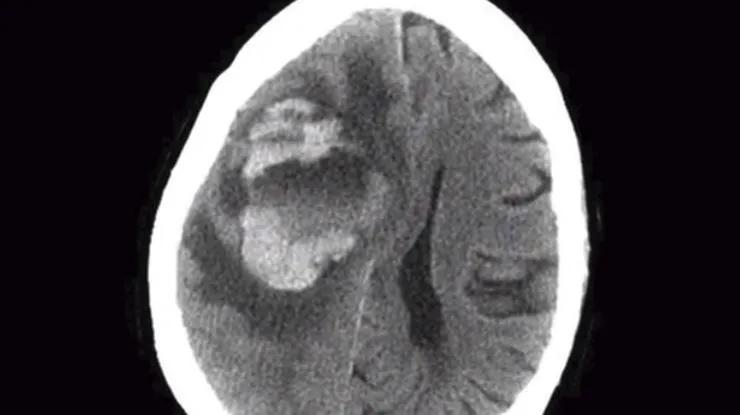

送院后电脑断层扫描显示其脑部有肿瘤,在切除硬币大小的肿块之后病人情况急转直下,病变迅速扩散。两周后再次手术,从脑部取出棒球大小的肿瘤,医生检查组织后发现是阿米巴变形虫作怪。此时病人已陷入昏迷,最终不治身亡。